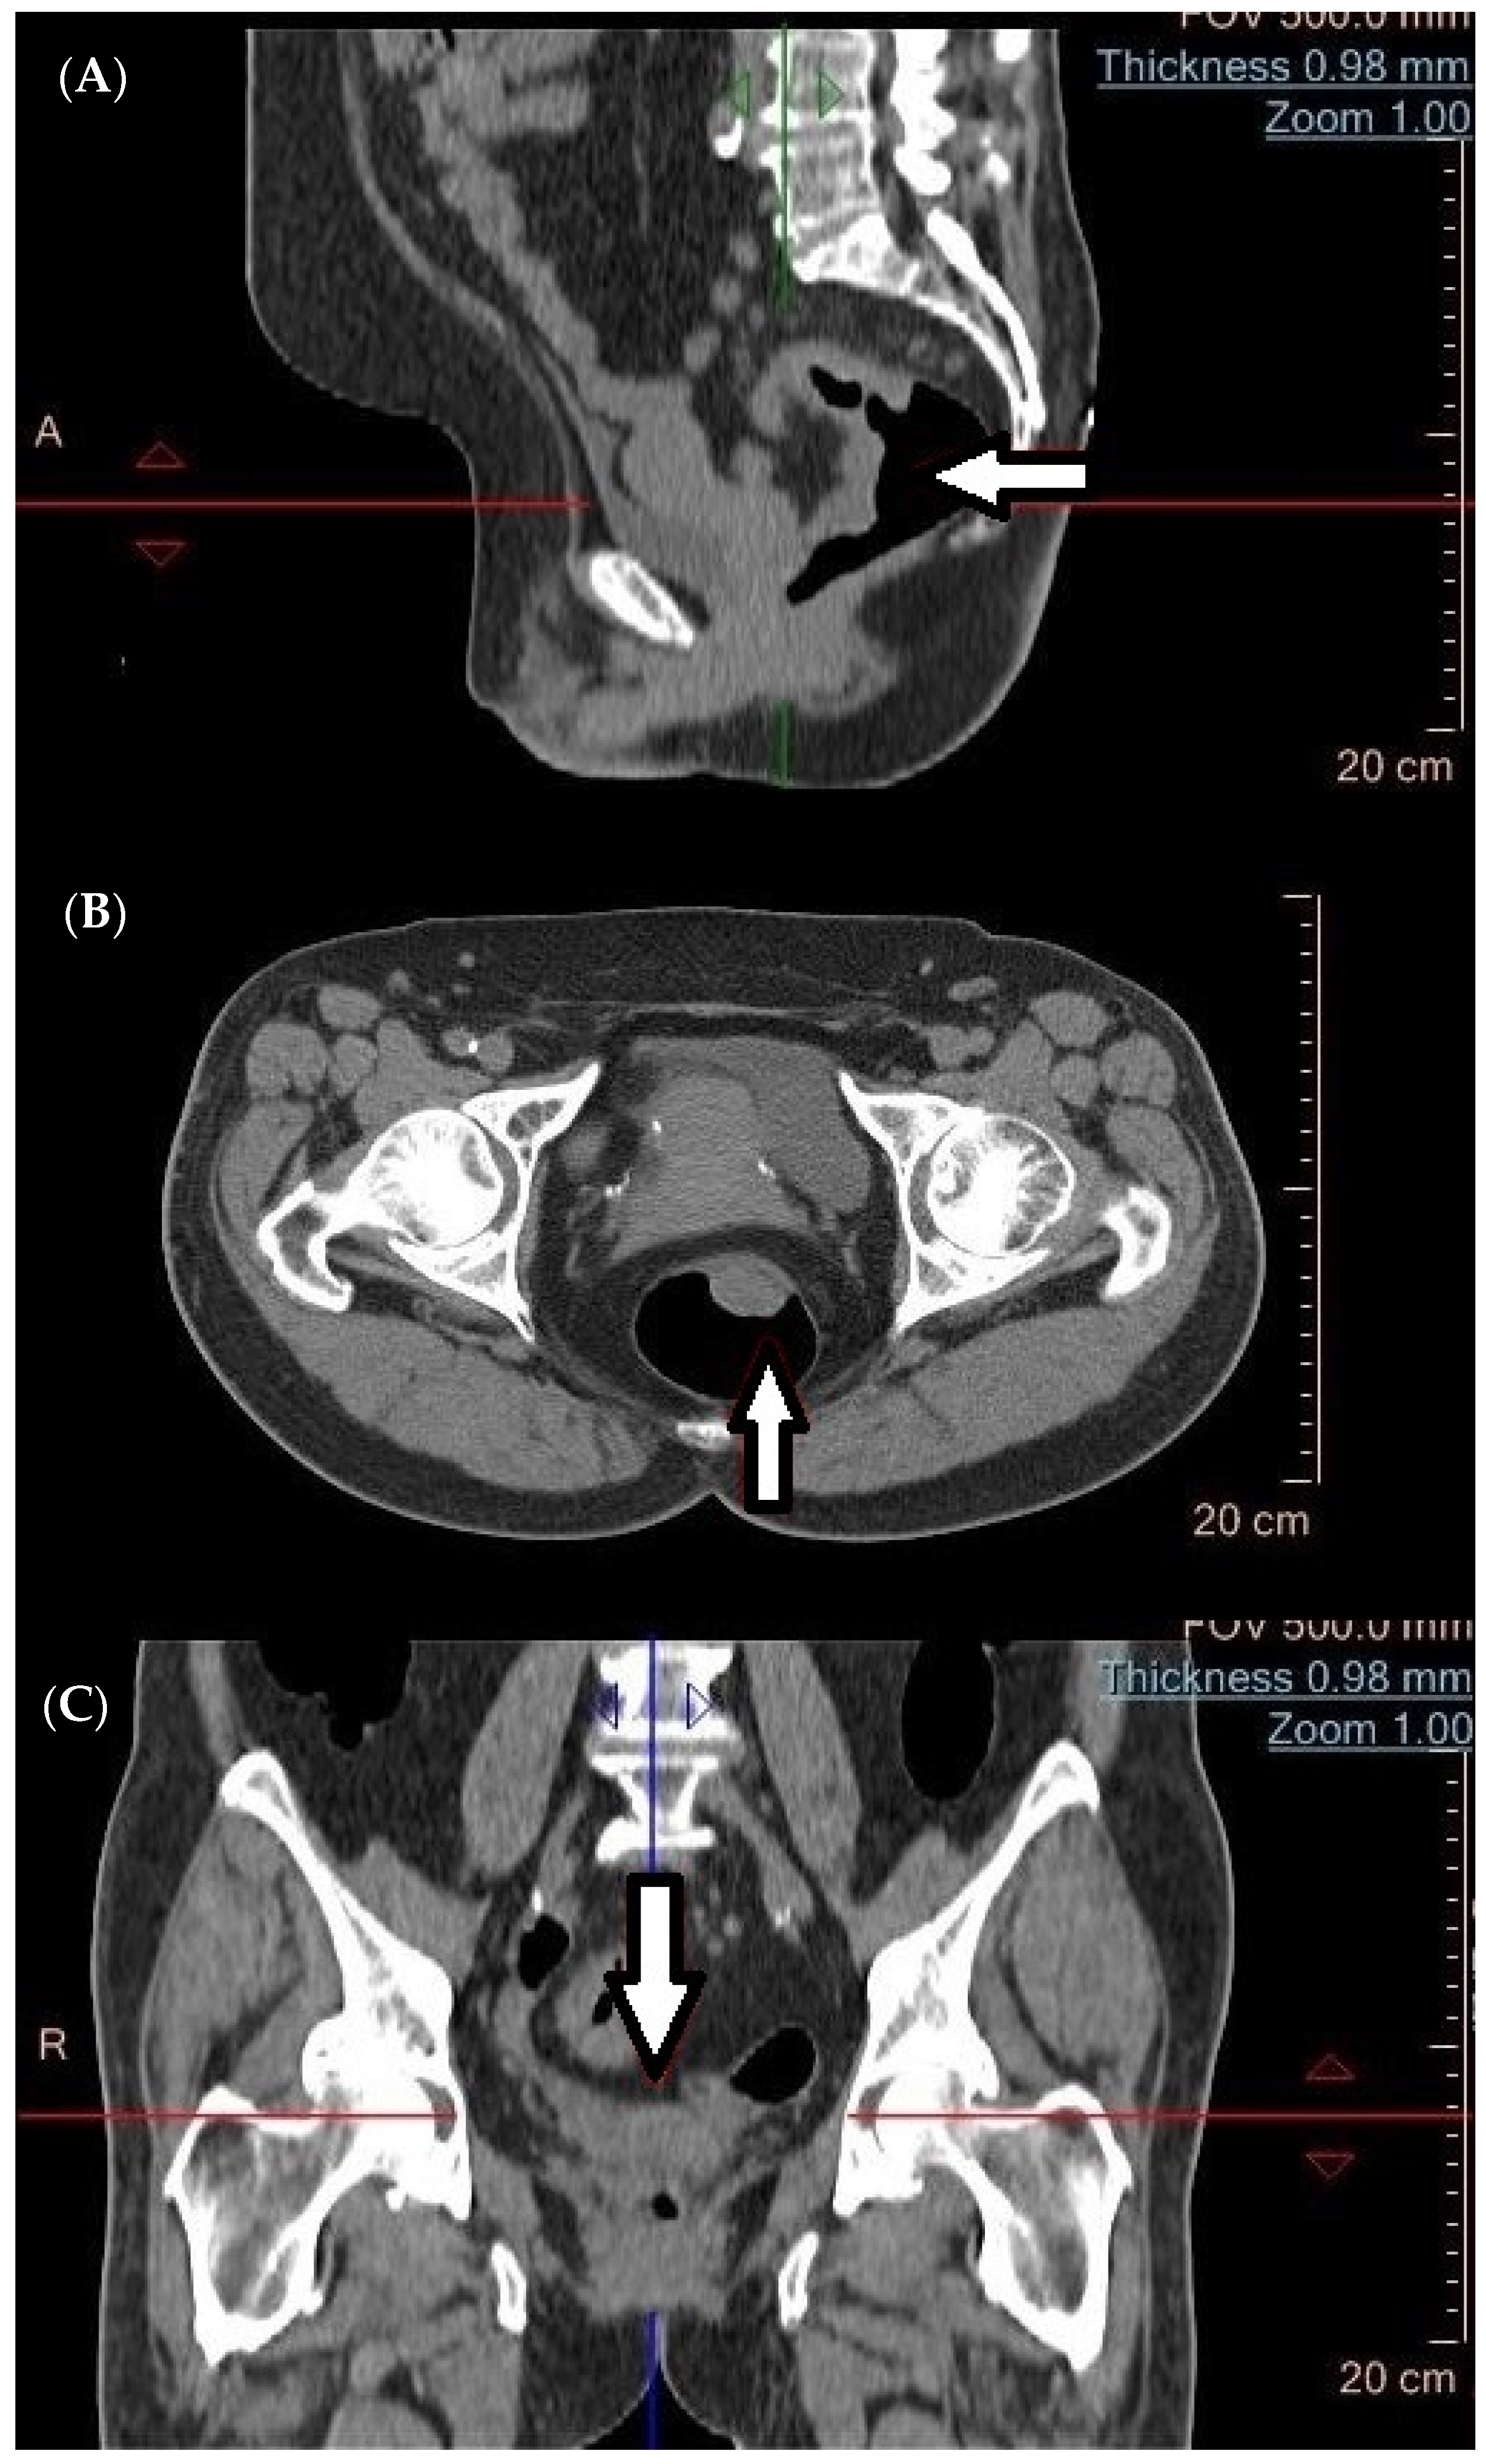

4. Computed Tomography (CT) in the Diagnosis of Metastatic Tumors

- Tan, C.H.; Iyer, R. Use of computed tomography in the management of colorectal cancer. World J. Radiol. 2010, 2, 151. [Google Scholar] [CrossRef]

- Klang, E.; Eifer, M.; Kopylov, U.; Belsky, V.; Raskin, S.; Konen, E.; Amitai, M.M. Pitfalls in diagnosing colon cancer on abdominal CT. Clin. Radiol. 2017, 72, 858–863. [Google Scholar] [CrossRef]

- Tang, Y.Z.; Alabousi, A. Incidental findings on staging CT for rectal cancer: Frequency, clinical significance and outcomes. Clin. Imaging 2023, 93, 14–22. [Google Scholar] [CrossRef]

- Colvin, H.; Lukram, A.; Sohail, I.; Chung, K.T.; Jehangir, E.; Berry, J.; Babu, H.; Hinson, F. The performance of routine computed tomography for the detection of colorectal cancer. Ann. R. Coll. Surg. Engl. 2013, 95, 473–476. [Google Scholar] [CrossRef]